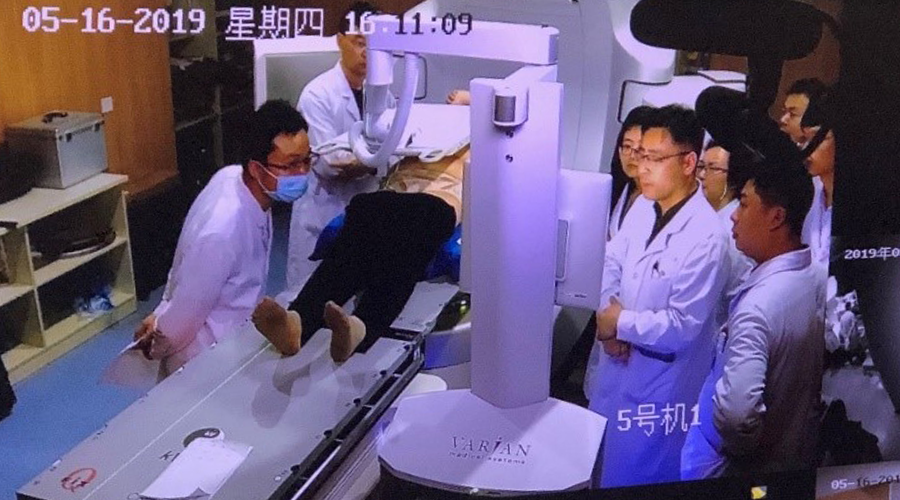

中国首例应用 Calypso 电磁定位肝脏大分割治疗的患者

与江苏省肿瘤医院医务人员和瓦里安应用培训工程师合影

首次治疗肝转移患者时物理师与治疗师在设置Calypso电磁定位系统